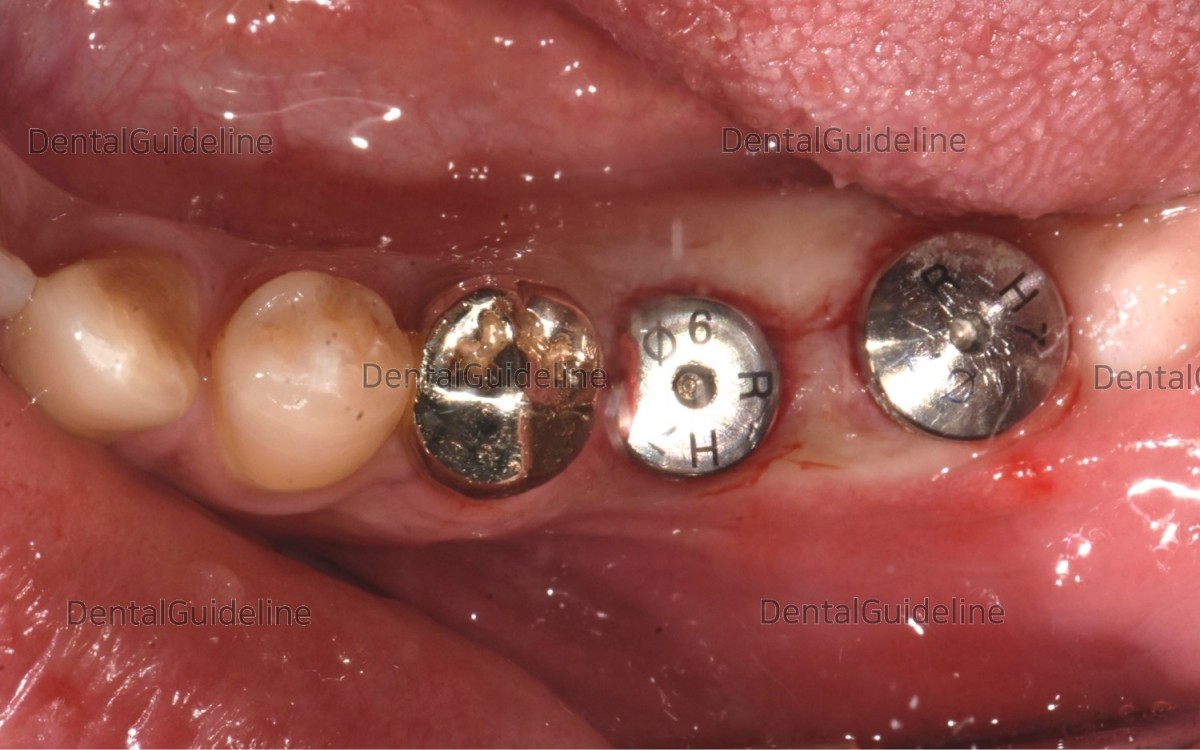

Implant uncovery utilizing the rotary tissue-punching instrument.

2 weeks after implant uncovery. The ISQ value was good enough at the implant in the molars.

After measurement of ISQ value, Healing abutment was exchanged in needed.